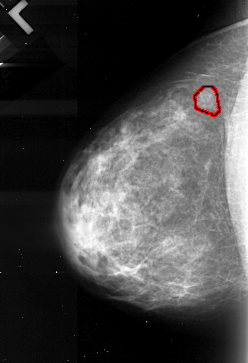

A_1103_1.LEFT_MLO

LEFT_MLO LINES 5191 PIXELS_PER_LINE 2986 BITS_PER_PIXEL 16 RESOLUTION 42 OVERLAY

FILE: A_1103_1.LEFT_MLO.OVERLAY

TOTAL_ABNORMALITIES 1

ABNORMALITY 1

LESION_TYPE MASS SHAPE LOBULATED MARGINS MICROLOBULATED

ASSESSMENT 4

SUBTLETY 4

PATHOLOGY MALIGNANT

TOTAL_OUTLINES 1

BOUNDARY